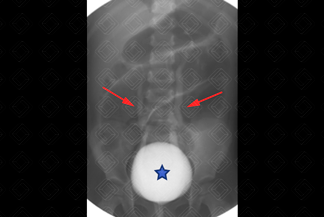

Texto alternativo para a imagem Figura 1. Créditos: Dra. Elazir Mota - Rio de Janeiro/RJ

Descrição das figuras 1 e 2: Fase de enchimento na qual observa-se bexiga opacificada (asterisco) por meio de contraste, onde já visualiza-se o início do refluxo bilateral (setas vermelhas). A radiografia final evidencia fase pós-miccional, com bexiga vazia e acentuação do refluxo vesicoureteral (grau II à direita e grau III, à esquerda). [cms-watermark]